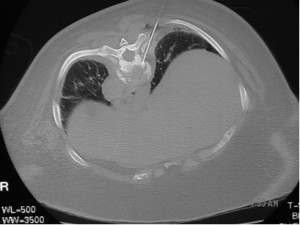

Sometimes it is necessary to biopsy a vertebra with metastatic disease for histopathology as in this woman in whom the T8 was the only evident site of destructive disease. Her primary site of cancer was unknown.

The approach to the percutaneous biopsy in this patient is not very different from the approach during vertebroplasty for thoracic vertebral compression fractures. Vertebroplasty is an effective method of relieving back pain in patients who have vertebral compression fractures.